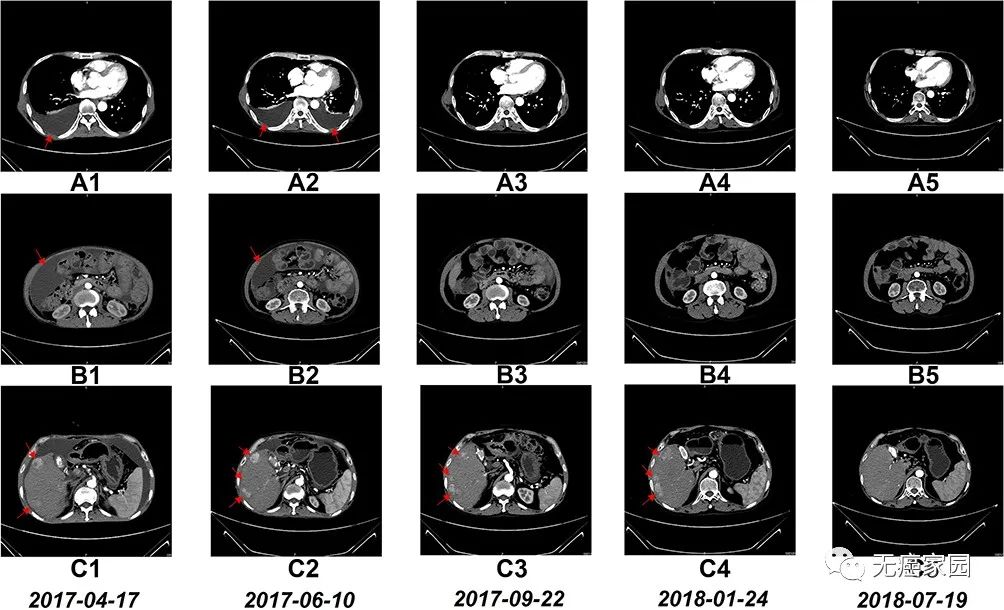

NK细胞治疗前和治疗期间的CT扫描结果

图A1~A5:CT扫描显示,6个疗程后胸腔积液完全消失;

图B1~B5:CT扫描显示,6个疗程后腹水几乎完全消失;

图C1~C5:CT:扫描显示,肝右叶多个肿瘤的大小在17 个疗程后显著缩小;